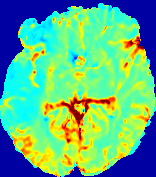

Figure 13: PIANO effectiveness and robustness testing: diffusion imaging via diffusion. Top row shows Dgtsuperscript𝐷gtD^{\text{gt}} used for simulating the ground truth pure diffusion. (a)-(f) refer to the results for D𝐷D estimated from the ground truth pure diffusion image time-series where Rician noise at levels 0%, 2%, 4%, 6%, 8%, 10% was added respectively.

Note this is likely not a spatially representative ground-truth for perfusion imaging, as it measures different effects from diffusion imaging. However, we still use it as a quasi-realistic pattern of diffusivity in the brain. We also added 2%, 4%, 6%, 8%, 10% levels of Rician noise to obtain simulations of ‘Diffusion Imaging’. The estimated Destsuperscript𝐷estD^{\text{est}} given concentrations of all noise levels for one patient are shown in Fig. 13, PIANO estimation results for all patients are summarized in Fig. 11 (b). Again, PIANO demonstrates its capability to recover the underlying diffusion field. In Fig. 13, when the noise level is increasing, some noisy patterns indeed appear in the associated Destsuperscript𝐷estD^{\text{est}}. Note that the ground truth diffusivity applied in this simulation experiment is about ten times larger than the diffusivity estimated in reality (Fig. 3, Fig. 4).